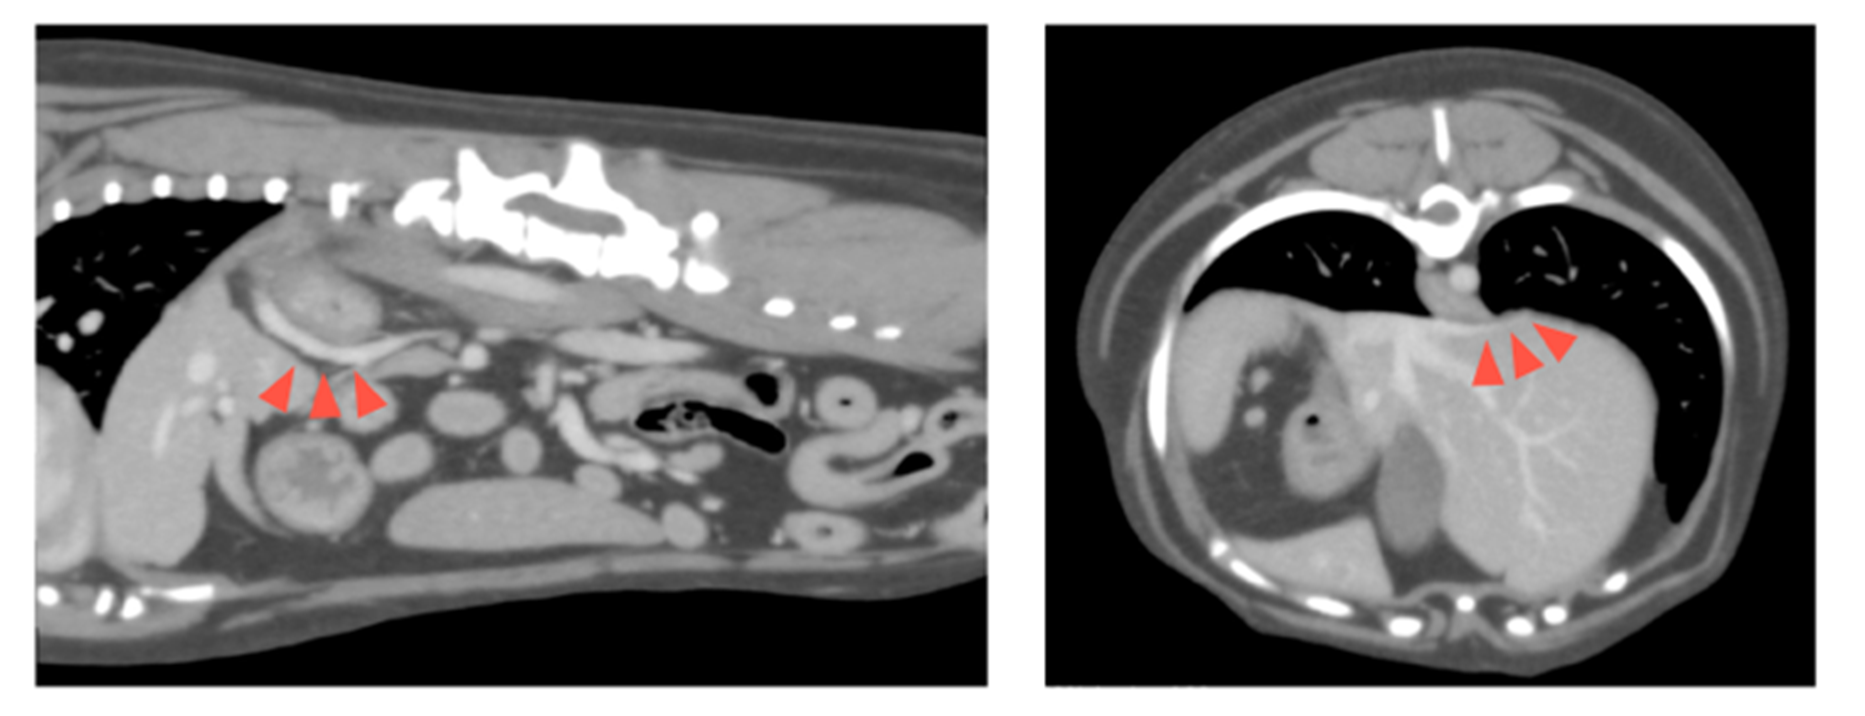

CT検査において、血管径約5mmの左胃静脈−横隔静脈−後大静脈シャントが見つかりました(赤矢頭)。

シャント血管によって肝臓に流入する血液の多くが全身循環に流れてしまうため、肝臓に流れる血液量が少なくなり、肝臓がやや小さく肝臓内の血管も発達が悪いことがわかりました。